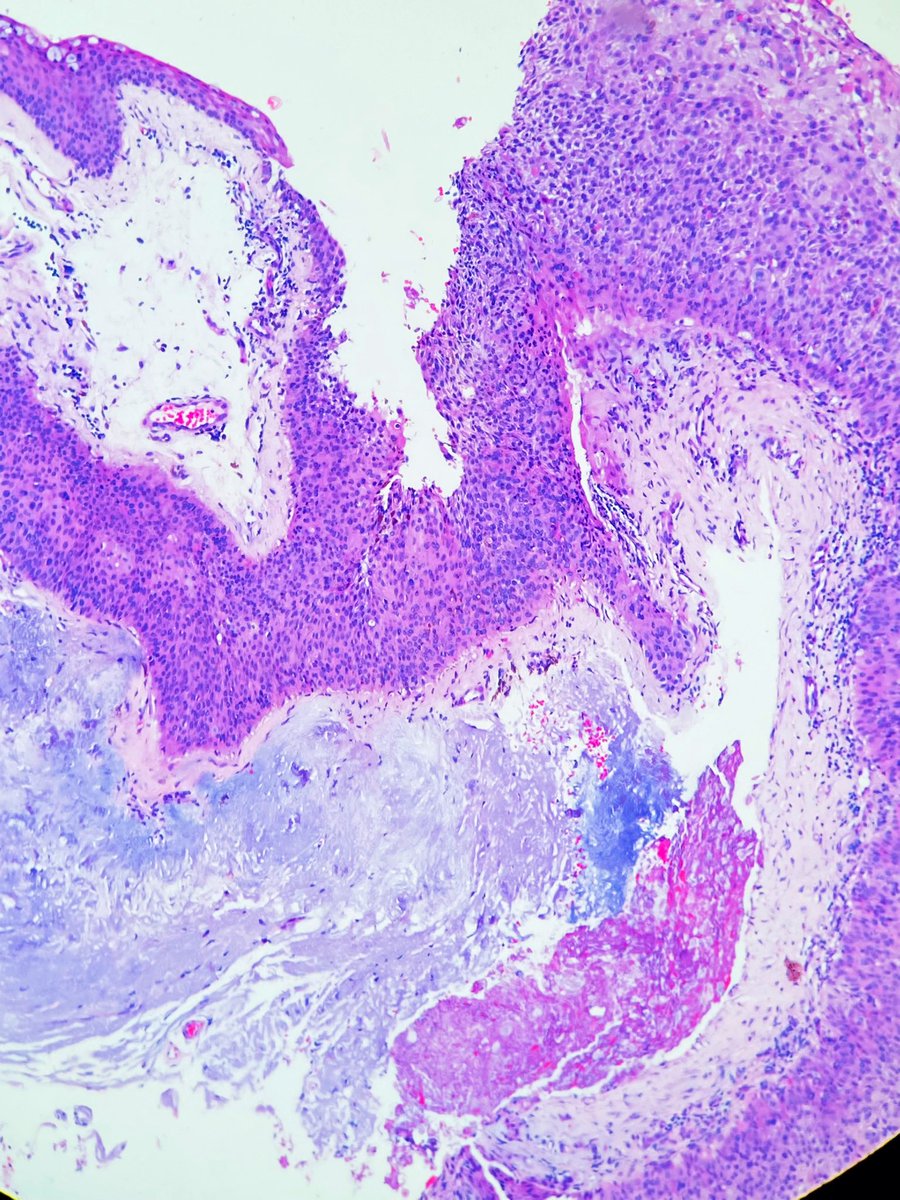

Cervical biopsy. Squamous intraepithelial lesion. What’s the grade? Why? . . . #medicine #anatomy #medschool #pathology #histology #medlife #histologia #path #pathologists #oncology

ClevesMario's tweet image. Cervical biopsy. Squamous intraepithelial lesion. What’s the grade? Why?

#medicine #anatomy #medschool #pathology #histology #medlife #histologia #path #pathologists #oncology